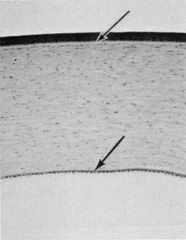

DESCEMET'S MEMBRANE

Descemet's membrane can be thought of as the basal lamina of the endothelium, and it varies in thickness in the human from approximately 3 μm at birth to 8 to 10 μm in adulthood (Fig. 17).86 The age-related growth and renewal of the membrane after injury indicate that it is an extracellular secretion of the endothelium. Descemet's membrane is stratified into distinct layers according to histologic appearance and immunohistochemical labeling: a thin, unbanded zone immediately adjacent to the interfacial matrix of the stroma (approximately 0.3 μm); a banded anterior zone (2 to 4 μm); and an unbanded posterior zone that may be as much as two-thirds the total thickness of Descemet's membrane in adults (> 4 μm). The banded and unbanded zone thicknesses vary, depending on the age of development and the species.66 Because the unbanded posterior zone is laid down by the endothelium over the course of a lifetime, it is a temporal record of the physiologic state of the endothelium. For example, unusual striated collagen banding occurs in the posterior zone in association with corneal disease such as Fuchs' dystrophy.87

Fig. 17. Full-thickness view of Descemet's membrane. Stromal collagen (C) with a keratocyte (F) is seen at top. Endothelium (E) is seen at bottom. Large box indicates anterior banded zone of 100-nm spaced collagen. Smaller boxes indicate occasional foci in the amorphous posterior unbanded zone. Arrows point to vesicles on the endothelial basal membrane. (Courtesy of Drs. Rodrigues, Waring, Hackett, and Donohoo.)

As noted previously, Descemet's membrane does not adhere strongly to the stroma, and it can be surgically dissected as a sheet. The randomly oriented collagen fibers in the interfacial matrix of the stroma have a densely matted appearance,40 and 22-nm thick fibers arising from the matrix penetrate Descemet's membrane to a depth of only 0.16 to 0.21 μm.88

The banded anterior zone is composed of numerous precisely aligned sheets forming a three-dimensional array or lattice.21 Each sheet of the array is constructed from triangular elements with densely staining nodes at the apices. The separation between nodes is approximately 100 to 110 nm. The highly ordered arrangement of the nodes causes the banded appearance seen in cross section. In the posterior unbanded zone, the appearance is of a homogeneous, fibrillogranular region. The anterior unbanded zone also has a fibrillogranular appearance but is extremely difficult to discern visually (Fig. 18).86

Fig. 18. Descemet's membrane is a composite of a nonbanded posterior portion with a granular appearance (DM) and an anterior portion with a banded appearance (arrows). At the interface between the stromal collagen (above) and Descemet's membrane is a narrow, unbanded, granular-appearing region. The endothelium (E) is seen below (37,000×). (Courtesy of Drs. Rodrigues, Waring, Hackett, and Donohoo.)